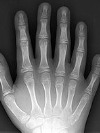

Asocia cada radionúclido con su equipo de detección correspondiente: Emisores de fotones, como el Tecnecio-99. Emisores de positrones, como el Flúor-18. El dispositivo en que se basan los activímetros para calcular la dosis exacta que se suministrará a cada paciente es: La disociación de materia. El centelleo. El fotomultiplicador. La cámara de ionización. El filtrado de imagen puede resultar de utilidad para reducir el efecto de: Ruidos exclusivamente. Ninguna de las respuestas es correcta. Ruidos y artefactos. Artefactos exclusivamente. Las imágenes generadas por una gammacámara al recibir emisiones de fotones: Se presentan en 3D, aunque puede dividirse para generar imágenes en 2D. Se presentan en 3D directamente. Se presentan en 2D, siempre. Se presentan en 2D, aunque puede procesarse para generar imágenes en 3D. Identifica el tipo de colimador para gammacámara que se muestra en la imagen: Colimador pinhole. Colimador convergente. Colimador en paralelo. Colimador divergente. ¿Qué característica define al modelo de colimador de la imagen anterior?. Se proporciona una imagen invertida y aumentada de alta resolución. Se aumenta el campo de visión, por lo que resulta de gran utilidad para estudiar tejidos grandes con una cámara pequeña. Se proporciona una imagen ampliada del campo de estudio. Tiene orificios perpendiculares al cristal, y no cambia la proporción de la imagen ni reduce la resolución espacial. El mecanismo de detección de un sistema de Tomografía por emisión de positrones (PET) se basa en: Detección de fotones X. Detección de excitaciones electrónicas. Detección de fotones por reacciones de aniquilación electrón-positrón. Detección de movimientos de precesión protónica. Debido al principio de conservación de la energía, podemos asegurar que al desintegrarse un electrón y un positrón: Se producirán un número desconocido de fotones gamma, con una energía de 511KeV cada uno. Se producirán 2 fotones gamma de energía desconocida. Se producirán 2 fotones gamma con una energía de 1,022MeV (1.022KeV) cada uno. Se producirán 2 fotones gamma con una energía de 511KeV cada uno. En un detector PET, para que dos fotones sean identificados como procedentes de la misma aniquilación: Deben detectarse fuera de la ventana de coincidencia. Deben detectarse dentro de la ventana de coincidencia. Los colimadores de las gammacámaras están generalmente compuestos por: Gases nobles, como el xenón o radón. Metales ligeros, como el aluminio o berilio. Elementos no metálicos, como el carbono o azufre. Metales de alta densidad, como el plomo o tungsteno. |